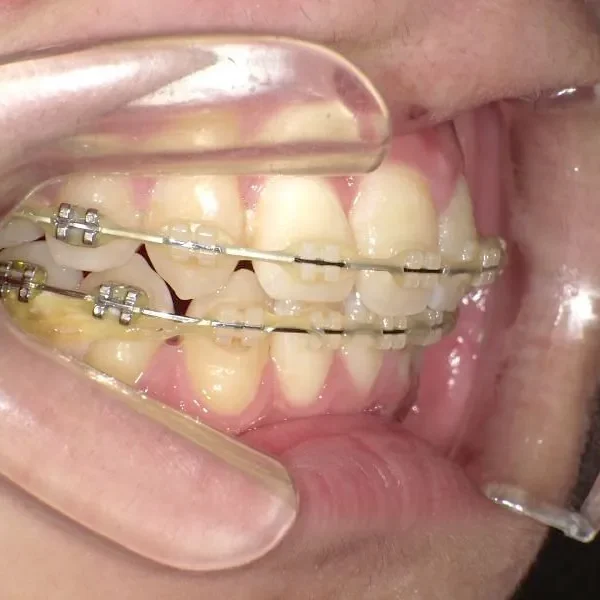

治療経過1

矯正用アンカースクリュー4本・マルチブラケット矯正装置

抜歯の有無 非抜歯 治療期間・通院回数 3年 1ヶ月 / 42回